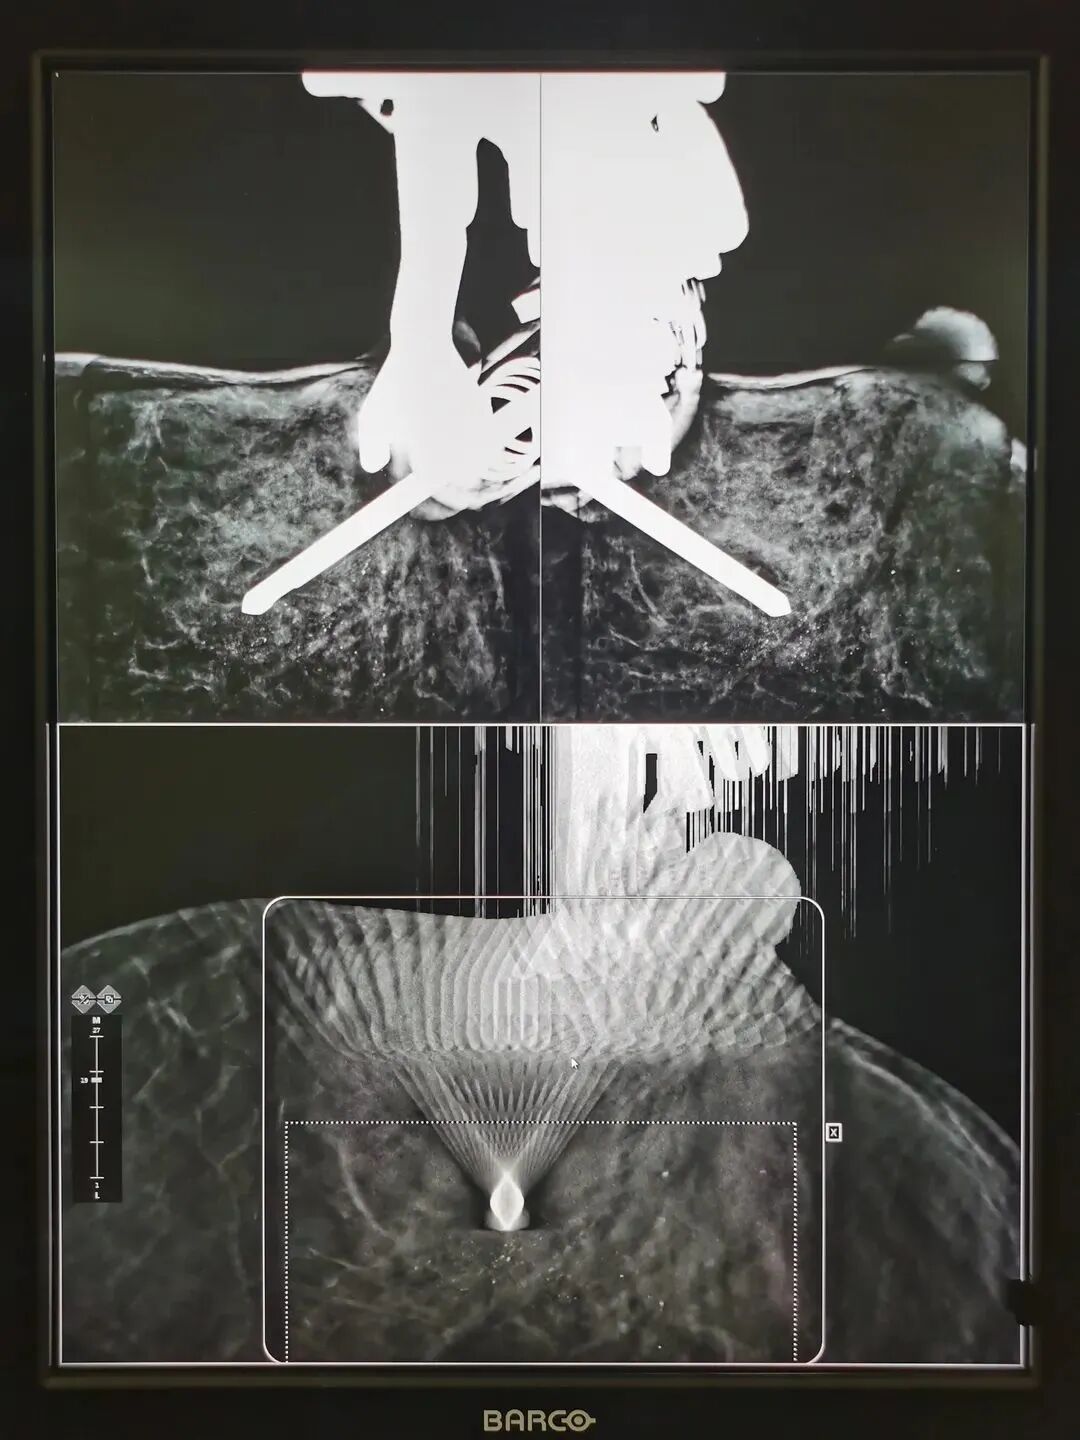

2021年6月9日,在上海交通大学医学院附属新华医院放射科汪登斌主任率领的乳腺影像团队成功开展了一例门诊患者乳腺微钙化的TOMO(断层)模式引导下乳腺3D立体定位活检(Tomosynthesis-guided stereotactic biopsy),国内鲜有开展,在上海尚属首例。该技术创伤小,定位准确,简便快捷,辐射剂量低,是一项安全、高效的影像学定位下微创活检技术。 3D数字乳腺断层成像立体定位活检装置 患者为39岁女性,近期乳腺X线摄影(俗称钼靶)体检发现左乳可疑微小钙化,乳腺超声及MRI检查均未见明确可疑恶性病变,患者迫切希望能够明确诊断,并尽可能采用微创方式。因此,汪登斌主任率领的乳腺团队对该患者病情进行了反复讨论,经与患者协商,决定对乳腺钙化灶实施TOMO(断层)模式引导下乳腺3D立体定位活检。 TOMO引导下乳腺立体定位活检系统 确定旋切刀位于钙化灶正前方进针 首先,技师先为患者拍摄定位片,汪登斌主任选择病灶最集中的层面确定穿刺点,一般系统根据病灶所处坐标的X、Y、Z三轴数据确定是否在安全值范围内,并按病灶深度和安全值,决定选择全槽或半槽,鉴于此例患者病灶位置较浅,汪主任决定活检取材时刀口采用半槽模式。随后消毒、安装旋切针、局麻、进针。通过第二次摄片,确认刀口到达病变区域后即进行旋切。病灶切除后进行最后一次摄影,评估旋切效果。对切除的活检标本进行摄片,并送达病理科。全程仅耗时13分钟。 左乳上部段样分布点状钙化 活检标本摄影显示成簇微小点状钙化 3D数字乳腺断层成像立体定位活检 VS 传统2D乳腺X线摄影定位活检 3D数字乳腺断层成像立体定位功能能够让医生在断层图像上发现隐匿性病变并直接进行定位活检操作,所以此功能能够让临床更准确地对乳腺病灶进行定位与活检; 3D数字乳腺断层成像立体定位功能仅需要一次断层扫描即可完成对病变的定位。相对于传统2D引导,立体定位能够减少拍摄次数,能够有效的提高技师的工作效率,提升整体定位活检等操作的效率,改善工作流程。 由于拍摄次数的减少,整体辐射剂量可降低30%—60%,提供了更为安全的定位活检操作。 汪登斌 主任医师 教授 科主任 博士生导师 研究方向: 乳腺、腹部影像学诊断;分子影像学及靶向探针研究 特需门诊: 周一、周四上午 详细介绍: 上海交通大学医学院附属新华医院放射科学科带头人、放射科主任、医学影像学教研室主任。国家住院医师规范化培训基地主任、上海市专科医师规范化培训基地主任。上海市卫生系统优秀学科带头人。在乳腺、腹部影像诊断方面具有较深的造诣。学术兼职包括中国妇幼保健协会放射医学专业委员会主任委员,中华医学会放射学分会乳腺专委会副主任委员,中国医师协会放射医师分会委员兼影像人工智能专委会副主任委员,中国研究型医院学会肿瘤影像专业委员会常务委员兼乳腺组组长,上海市医学会放射学分会副主任委员兼乳腺组、儿科组、分子影像组顾问,上海市中西医结合学会医学影像学专业委员会副主任委员,上海健康医学院教育委员会委员,上海市卫生系统高级专业技术职务评审评委,国家科技部重点研发计划等评审专家,担任7本核心期刊的常务编委或编委,以及北美放射学会(RSNA)、美国放射学会(ARRS)、欧洲放射学会(ESR)通讯会员。在国内较早开展乳腺病灶的影像学定位并独立完成活检(国内其他医院一般均由外科医师操作),显著提高了早期乳腺癌的诊断率。同时还是我国“乳腺MRI检查共识”执笔人;先后主持国家级及省部级课题近20项,获得包括上海市卫生系统优秀学科带头人培养计划在内的人才计划7项,发表学术论文150余篇,其中SCI论文50余篇。领衔完成科研成果:“乳腺疾病影像学系列研究”,作为第一完成人获得“上海市科技进步奖三等奖”及“上海医学科技奖三等奖”各1项;作为主要完成人获得“国家科技进步二等奖” 等奖项多项。曾受邀在2016年韩国放射学年会,2019年中日韩乳腺影像会议及2019年RSNA上做演讲,阐述我国乳腺癌筛查、诊疗诊断及乳腺影像学发展状况等,受到国际同行的肯定。 上海交通大学医学院附属新华医院乳腺外科 Department of Breast Surgery,Xinhua Hospital 上海交通大学医学院附属新华医院乳腺外科是一个集乳腺疾病早期诊断、精准手术、规范综合治疗、教学、科研和预防为一体的专业学科,是国家级普通外科临床重点专科的重要组成部分,也是上海交通大学乳腺癌临床医学中心组成单位,承担本科、硕士、博士研究生和规范化住院医师的培训,是新华医院重点发展的学科。本专业所有医生均具有研究生以上学历,拥有高级职称5名,主治医师2名,住院医师5名,硕士3名,博士9名,博士后1名。硕士研究生导师2名,博士研究生导师1名,博士后指导教师1名。 新华医院乳腺外科目前是国内著名的乳腺外科手术学培训中心,是中国乳房重建外科联盟主席单位、中国乳腺外科微创治疗与腔镜手术联盟副主席单位、最后一公里·精准乳腺整复万名医师培训计划负责单位、剑在弦上·规范化乳腺外科手术学培训全国巡讲项目负责单位、母乳喂养指导师师资培训全国示范中心、与美丽同行志愿者联盟主席单位、中国妇女发展基金会、与美丽同行·女性健康关爱计划负责单位。 早期诊断:在乳腺肿瘤的早期诊断和精准定位方面居于国内领先水平,拥有目前国内辐射最低的乳腺X线数字摄片系统和精度1mm的计算机定位系统。是华东地区唯一能同时开展乳腺微小肿瘤超声、X线和磁共振钩针定位和微创旋切的单位。 外科手术:在乳腺肿瘤功能性美学重建手术和规范化综合治疗上,积累了鲜明的学术优势,乳腺癌保乳和I期重建比例大于60%,居于国际同步水平,科室成员在国内60多个学术委员会兼职。我们团队在根治肿瘤的前提下,强调保护乳房功能的完整,注重人文、心理学和美学的融合,在乳腺外科手术学上进行了系统的创新,尤其是在保留感觉神经的功能性腋淋巴结清除术、腋窝无痕技术前哨淋巴结示踪活检手术、乳房表面无痕的乳腺癌保乳整复外科手术、中央区乳腺癌的保乳修复、避免术后乳房外形的塌陷畸形、合并乳腺肿瘤的乳头内陷的畸形纠正、保留乳腺手术后哺乳功能等方面处于国内领先水平,形成了具有“精准·精心·精美”特征的“新华模式”,受邀在国内200多个会议主题演讲,被国内同道广泛认可和借鉴,享有“精准新华·精美乳房”的社会盛誉。 腔镜微创手术:目前男性乳房发育从男性的青春期到老年期有较高的发生率。主要原因有青春期的性激素紊乱,药物的副作用导致雄激素降低,肝功能降低造成激素代谢异常等等。男性发育的乳腺组织及周围脂肪,在体型外观上呈现女性化表现,对男性的自信心造成负面影响外。此外,增生的腺体同时存在癌变的风险。我科在上海地区首先采用腔镜微创及溶脂技术,通过隐蔽切口,重塑正常的男性胸部,帮助男性提升自信心及预防癌变风险。 国际化同步药物治疗:依据循证医学和国际乳腺癌临床实践指南与共识,实现国际同步的规范化、个体化的化疗、内分泌和靶向药物等综合治疗。在局部晚期乳腺癌的术前新辅助化疗和复发转移性乳腺癌的综合治疗方面也积累了丰富的经验。近年在乳腺炎症性疾病,特别是哺乳指导、急性乳腺炎、乳腺脓肿和非哺乳期慢性乳腺炎症性疾病的非手术治疗上积累了越来越多的经验。

三维立体定位